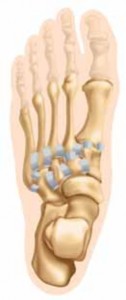

DEFINITION A Lisfranc injury refers to bony or ligamentous compromise of the tarsometatarsal and intercuneifo…